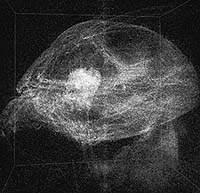

| Рисунок 2. Объемная трехмерная визуализация головы муравья. Воссозданная с помощью метода стохастической выборки для генерации одновременно трех изобразительных слоев. Экспериментальные данные, в Арагонской национальной лаборатории, составляют 256 проекций размером 512 x 512 пикселов, а в результате реконструкции создается трехмерное изображение размером 512 x 512 x 512 пикселов. Сбор данных занимает 15 минут, генерация окончательного результата - около 10 минут, с применением для реконструкции 32 процессоров. |

Рассмотрим следующую ситуацию. Ученый, изучая, увеличенное изображение биологического образца, как показано на рисунке 2, поворачивает ручку настройки научного прибора с тем, чтобы более детально рассмотреть те области, которые представляют для него наибольший интерес. Его коллега замечает какую-то особенность и ученый передает ей управление, чтобы она могла внимательнее рассмотреть то, что ее заинтересовало. Они обсуждают увиденное и сравнивают результаты с другим образцом, который видели чуть раньше.